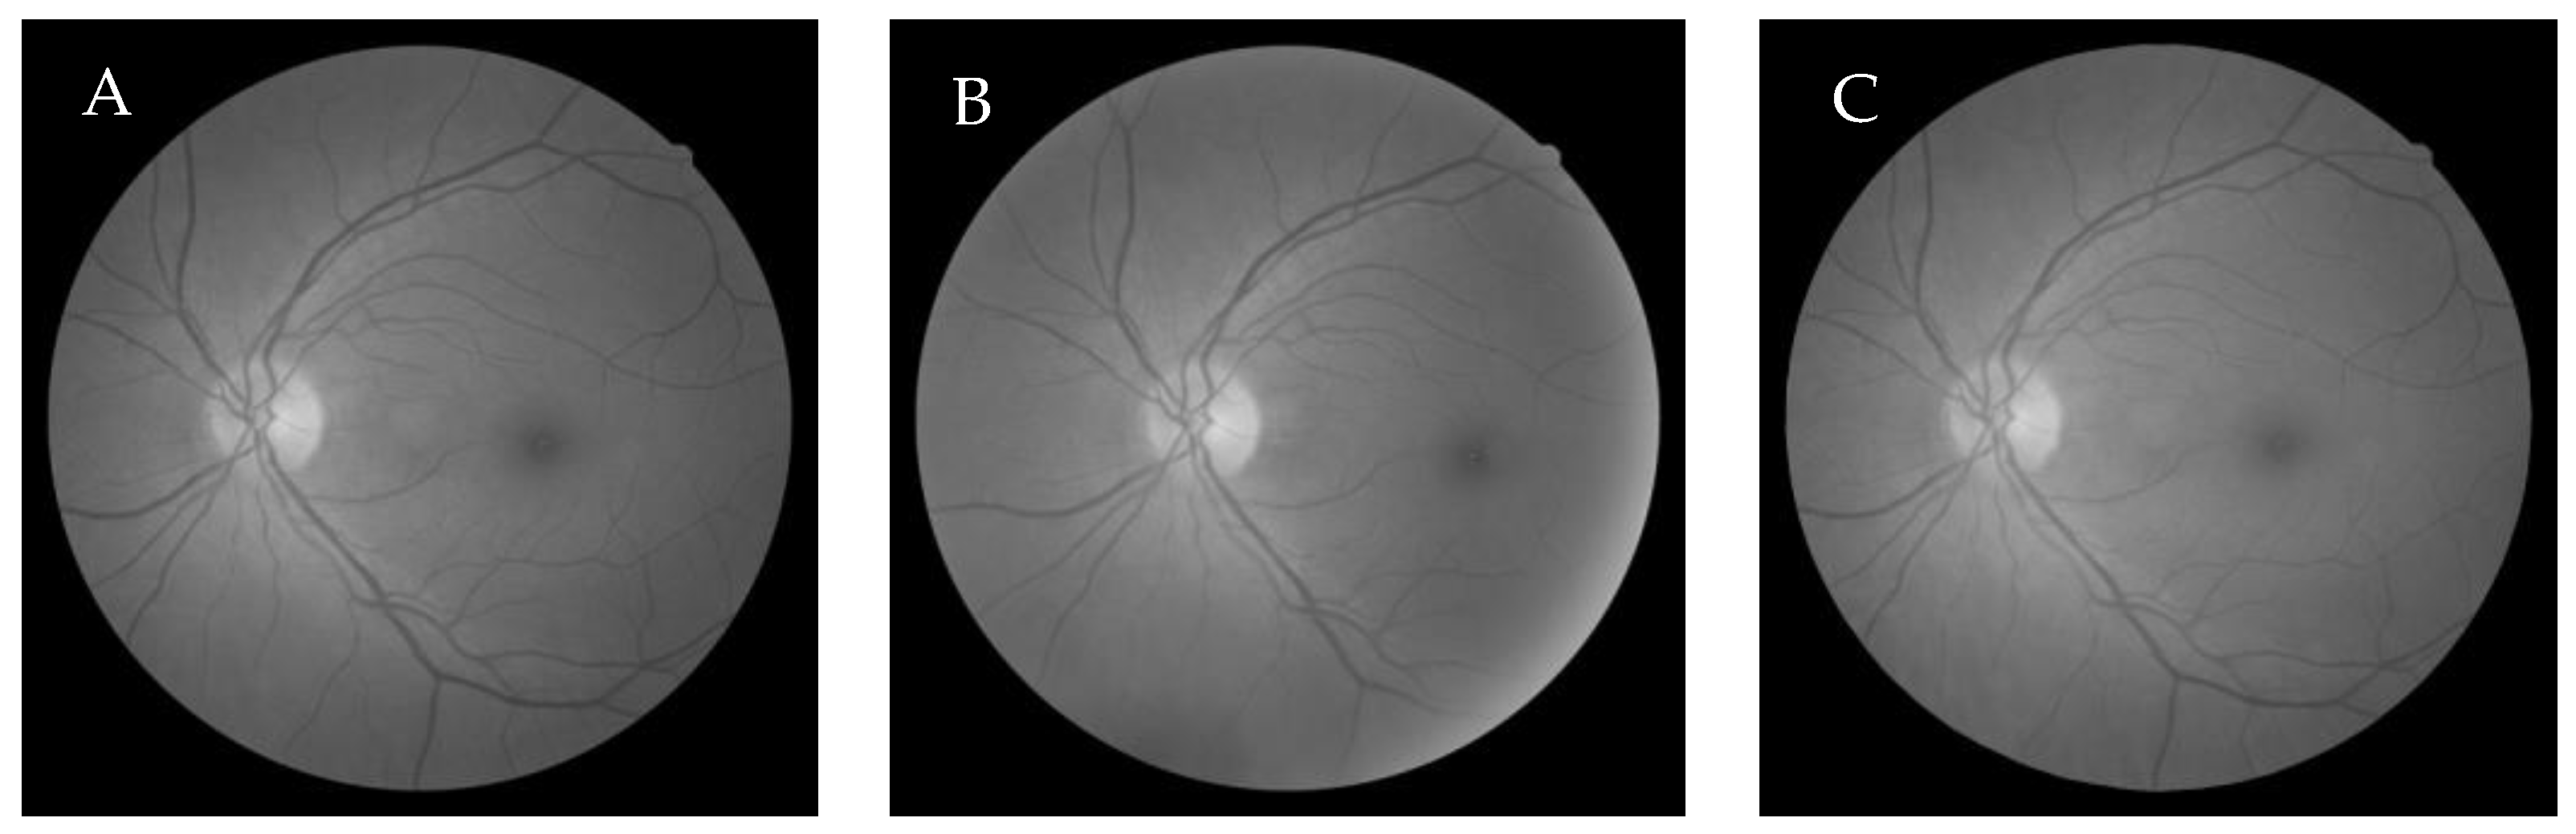

6.1. Dataset

6.2.1. Grey-Wolf Optimization-Based Wang’s Demons Registration